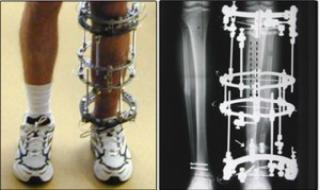

ضمن سعيها الدؤوب لإدخال كلّ ما هو جديد مواكبةً للتطوّر الطبّي أعلن مديرُ مركز الكفيل الأوروبّي في مستشفى الكفيل التخصّصي التابع للعتبة العبّاسية المقدّسة الدكتور صفاء الحسينيّ أنّه: "تمّ إدخال تقنية المثبّت الخارجي ليزاروف (Ilizarov apparatus) لعلاج حالات الحوادث والكسور المعقّدة والمتعدّدة وغير الثابتة، وأيضاً علاج التهابات العظام الجرثوميّة وحالات القصر الشديد الناتجة عن التشوّهات الخلقيّة مثل قصر أحد الساقين أو تقوّس الساقين أو قصور في النموّ، وهي من التقنيّات الحديثة المستخدمة في أغلب المستشفيات العالميّة.

وأضاف: "إنّ إصلاح ومعالجة تشوّهات العظام باستخدام هذه التقنية تكون بعمل جراحةٍ يتمّ فيها تركيب مثبّت خارجيّ ثمّ يتمّ عمل شقٍّ في العظام بطريقةٍ معيّنة بحيث يتحوّل هذا الشق الى ما يُشبه مركز النموّ في الأطفال، ثمّ يتمّ توجيه النموّ في هذا المكان بواسطة المثبّت الخارجي عن طريق إطالة الأنسجة بسرعة ممّا ينتج بالتدريج أنسجةً جديدة في العظام والأعصاب والشرايين والعضلات والجلد وبالتالي يُمكن التحكّم في وضع العظام وتثبيتها دون الحاجة لعمل فتحة جراحيّة، ثمّ يُزال المثبّت الخارجي بعد اكتمال التئام الكسور".

وبيّن: "يُمكن استخدام هذه التقنيّة لتثبيت الكسور المفتوحة، تثبيت (سمكرة) المفاصل، تطويل العظام، تثبيت العظام بعد جراحات تصليح تشوّهات العظام".

أمّا الطبيبُ الروسيّ ألكسندر ميتروفانوف المتواجد حاليّاً في مستشفى الكفيل فقد أضاف من جانبه: "إنّ الجهاز يُعتبر من تقنيّات الطبّ الحديث في علاج الكسور المعقّدة للعظام، وإنّ للجهاز قابليّة إضافة الطول بين (15سم) الى (30سم) وهو يُستخدم على شكل مثبّت خارجيّ حلقي في جراحة العظام والكسور المعقّدة".